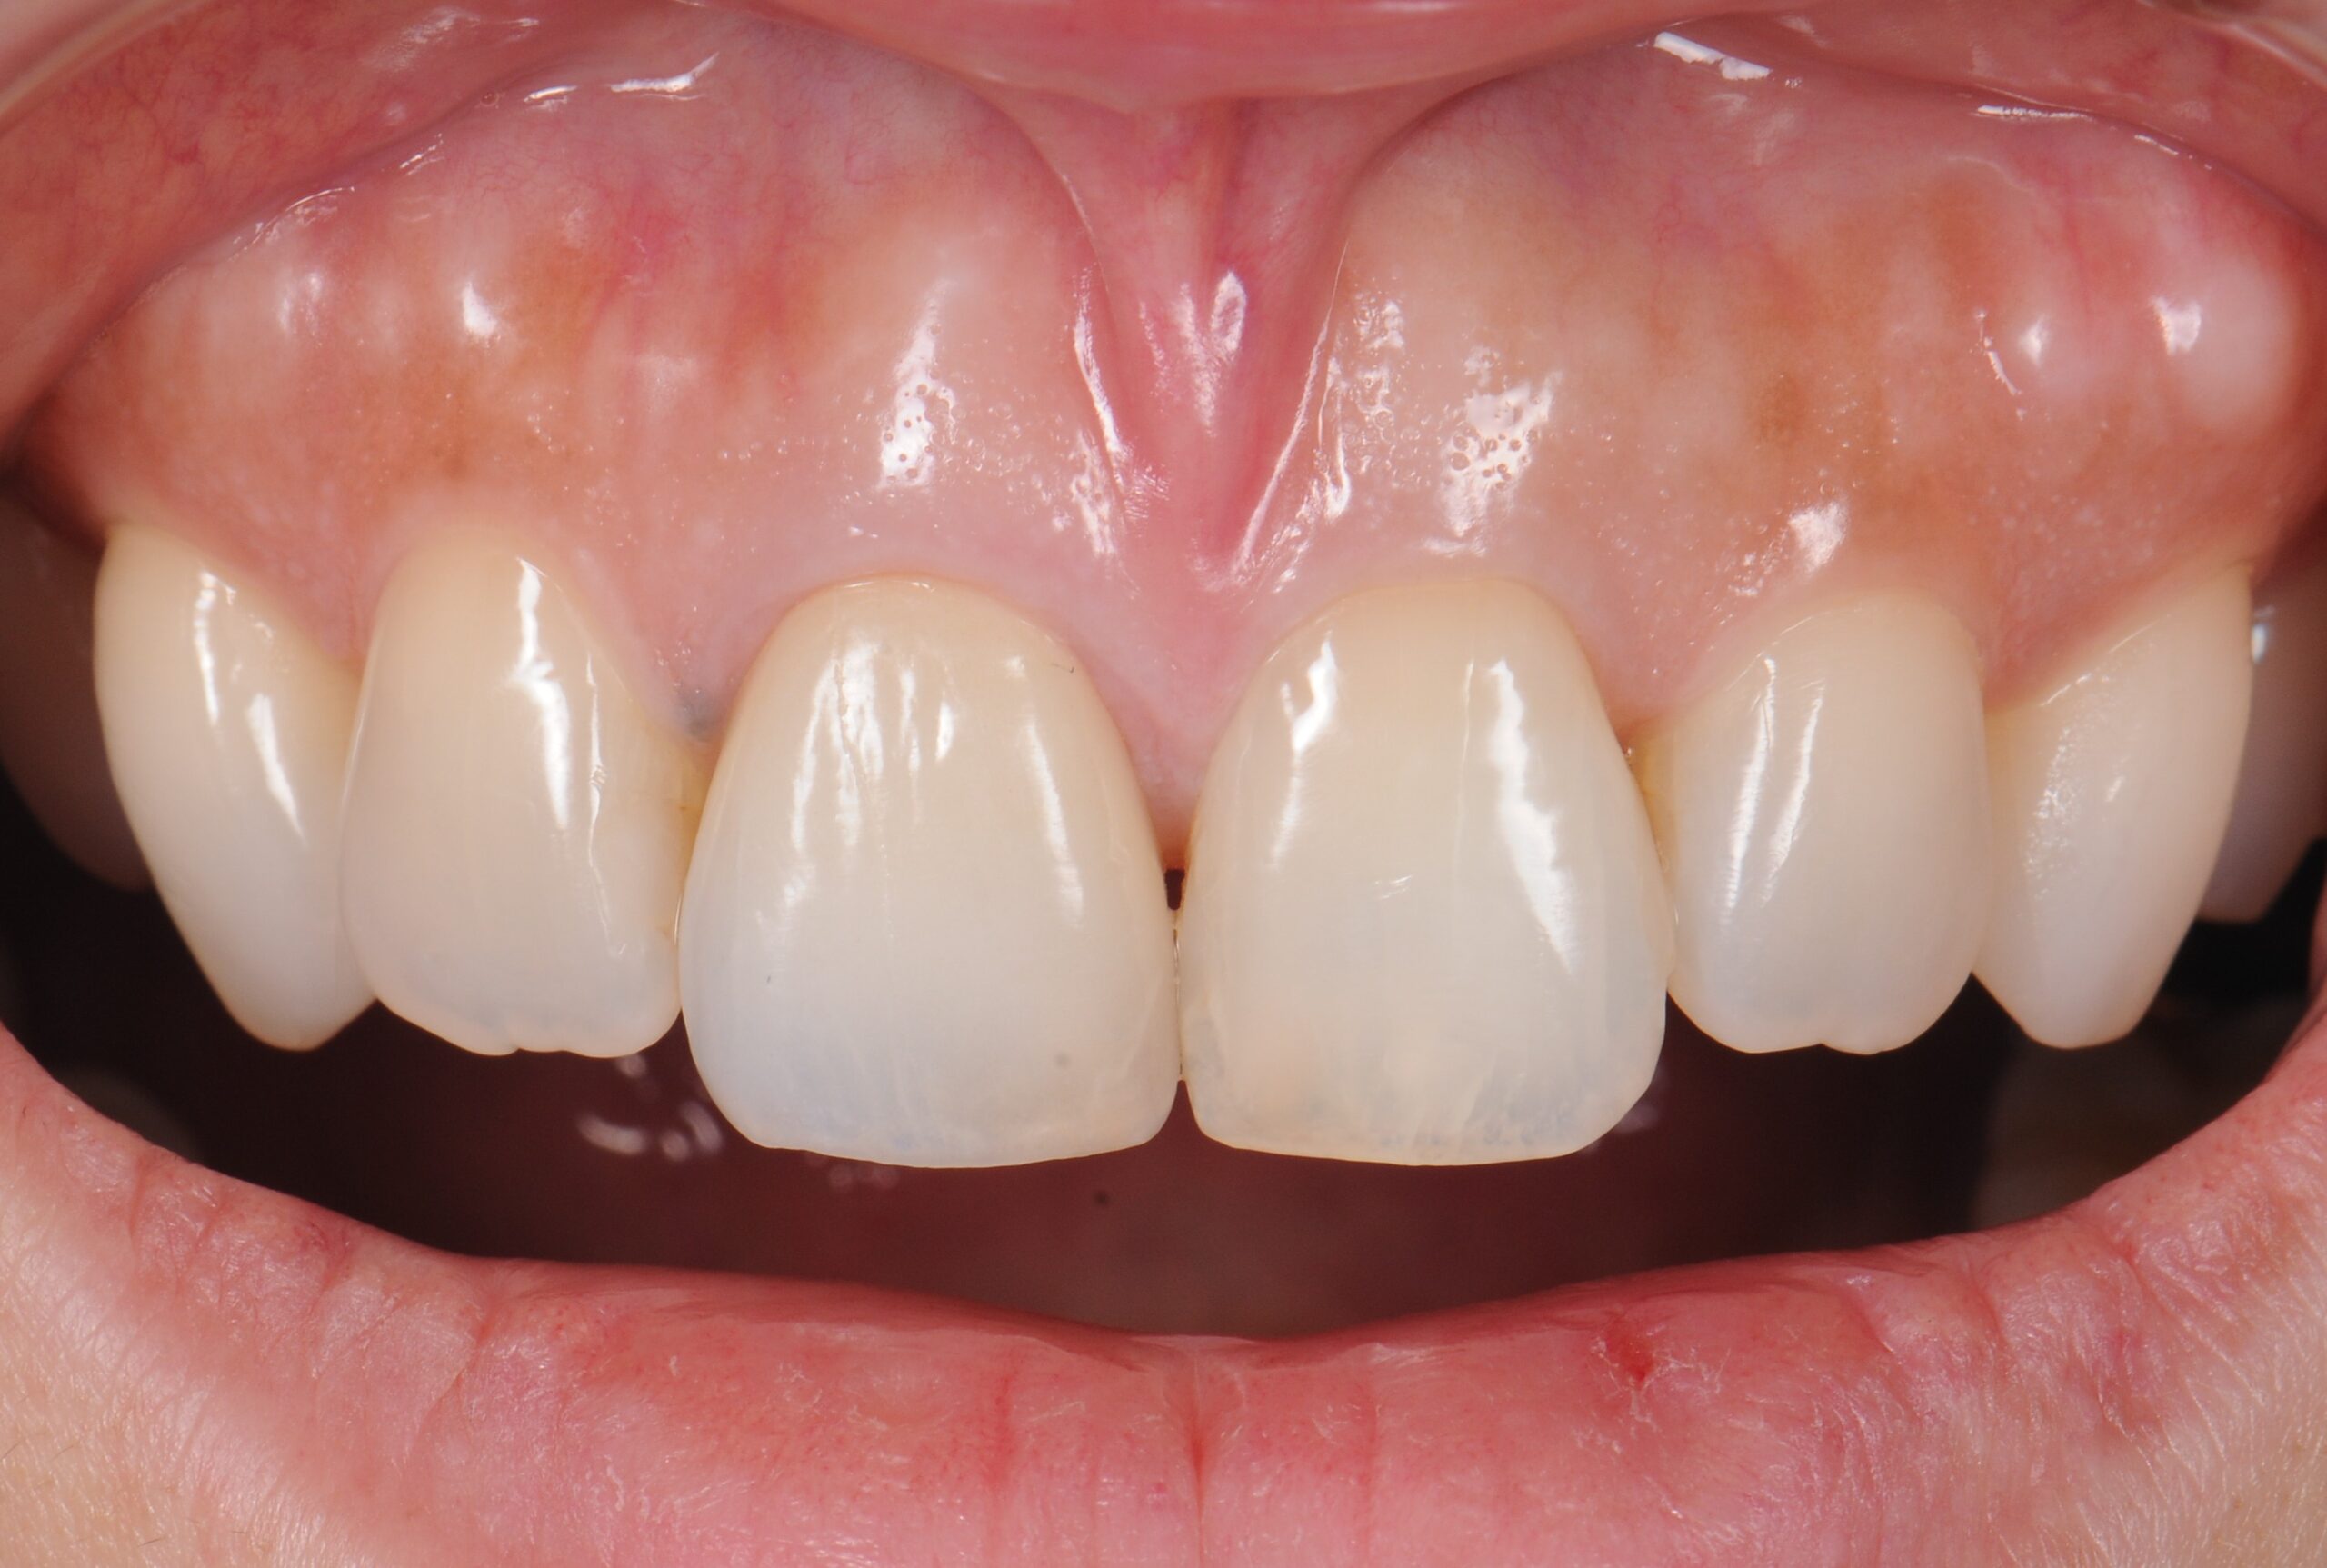

case4 症例(セラミッククラウン前歯)

治療後

| 費用(税込み) | 1本あたり154,000円×5本 |

|---|---|

| メリット・デメリット | デメリット 歯質を削合する必要がある |

| 治療回数 | 20回 |

| 主訴 | 歯の形態をきれいにしたい |